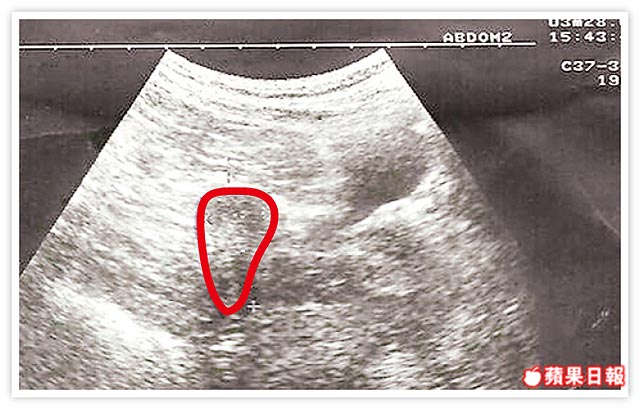

單人房硬塞2人 子宮像牛角 女流產4次 雙角子宮「比正常小」 醫:做子宮整形可改善       字級: 最小字型預設最大字型 人氣(7844)轉寄(0)引用(28) 分享: 分享...